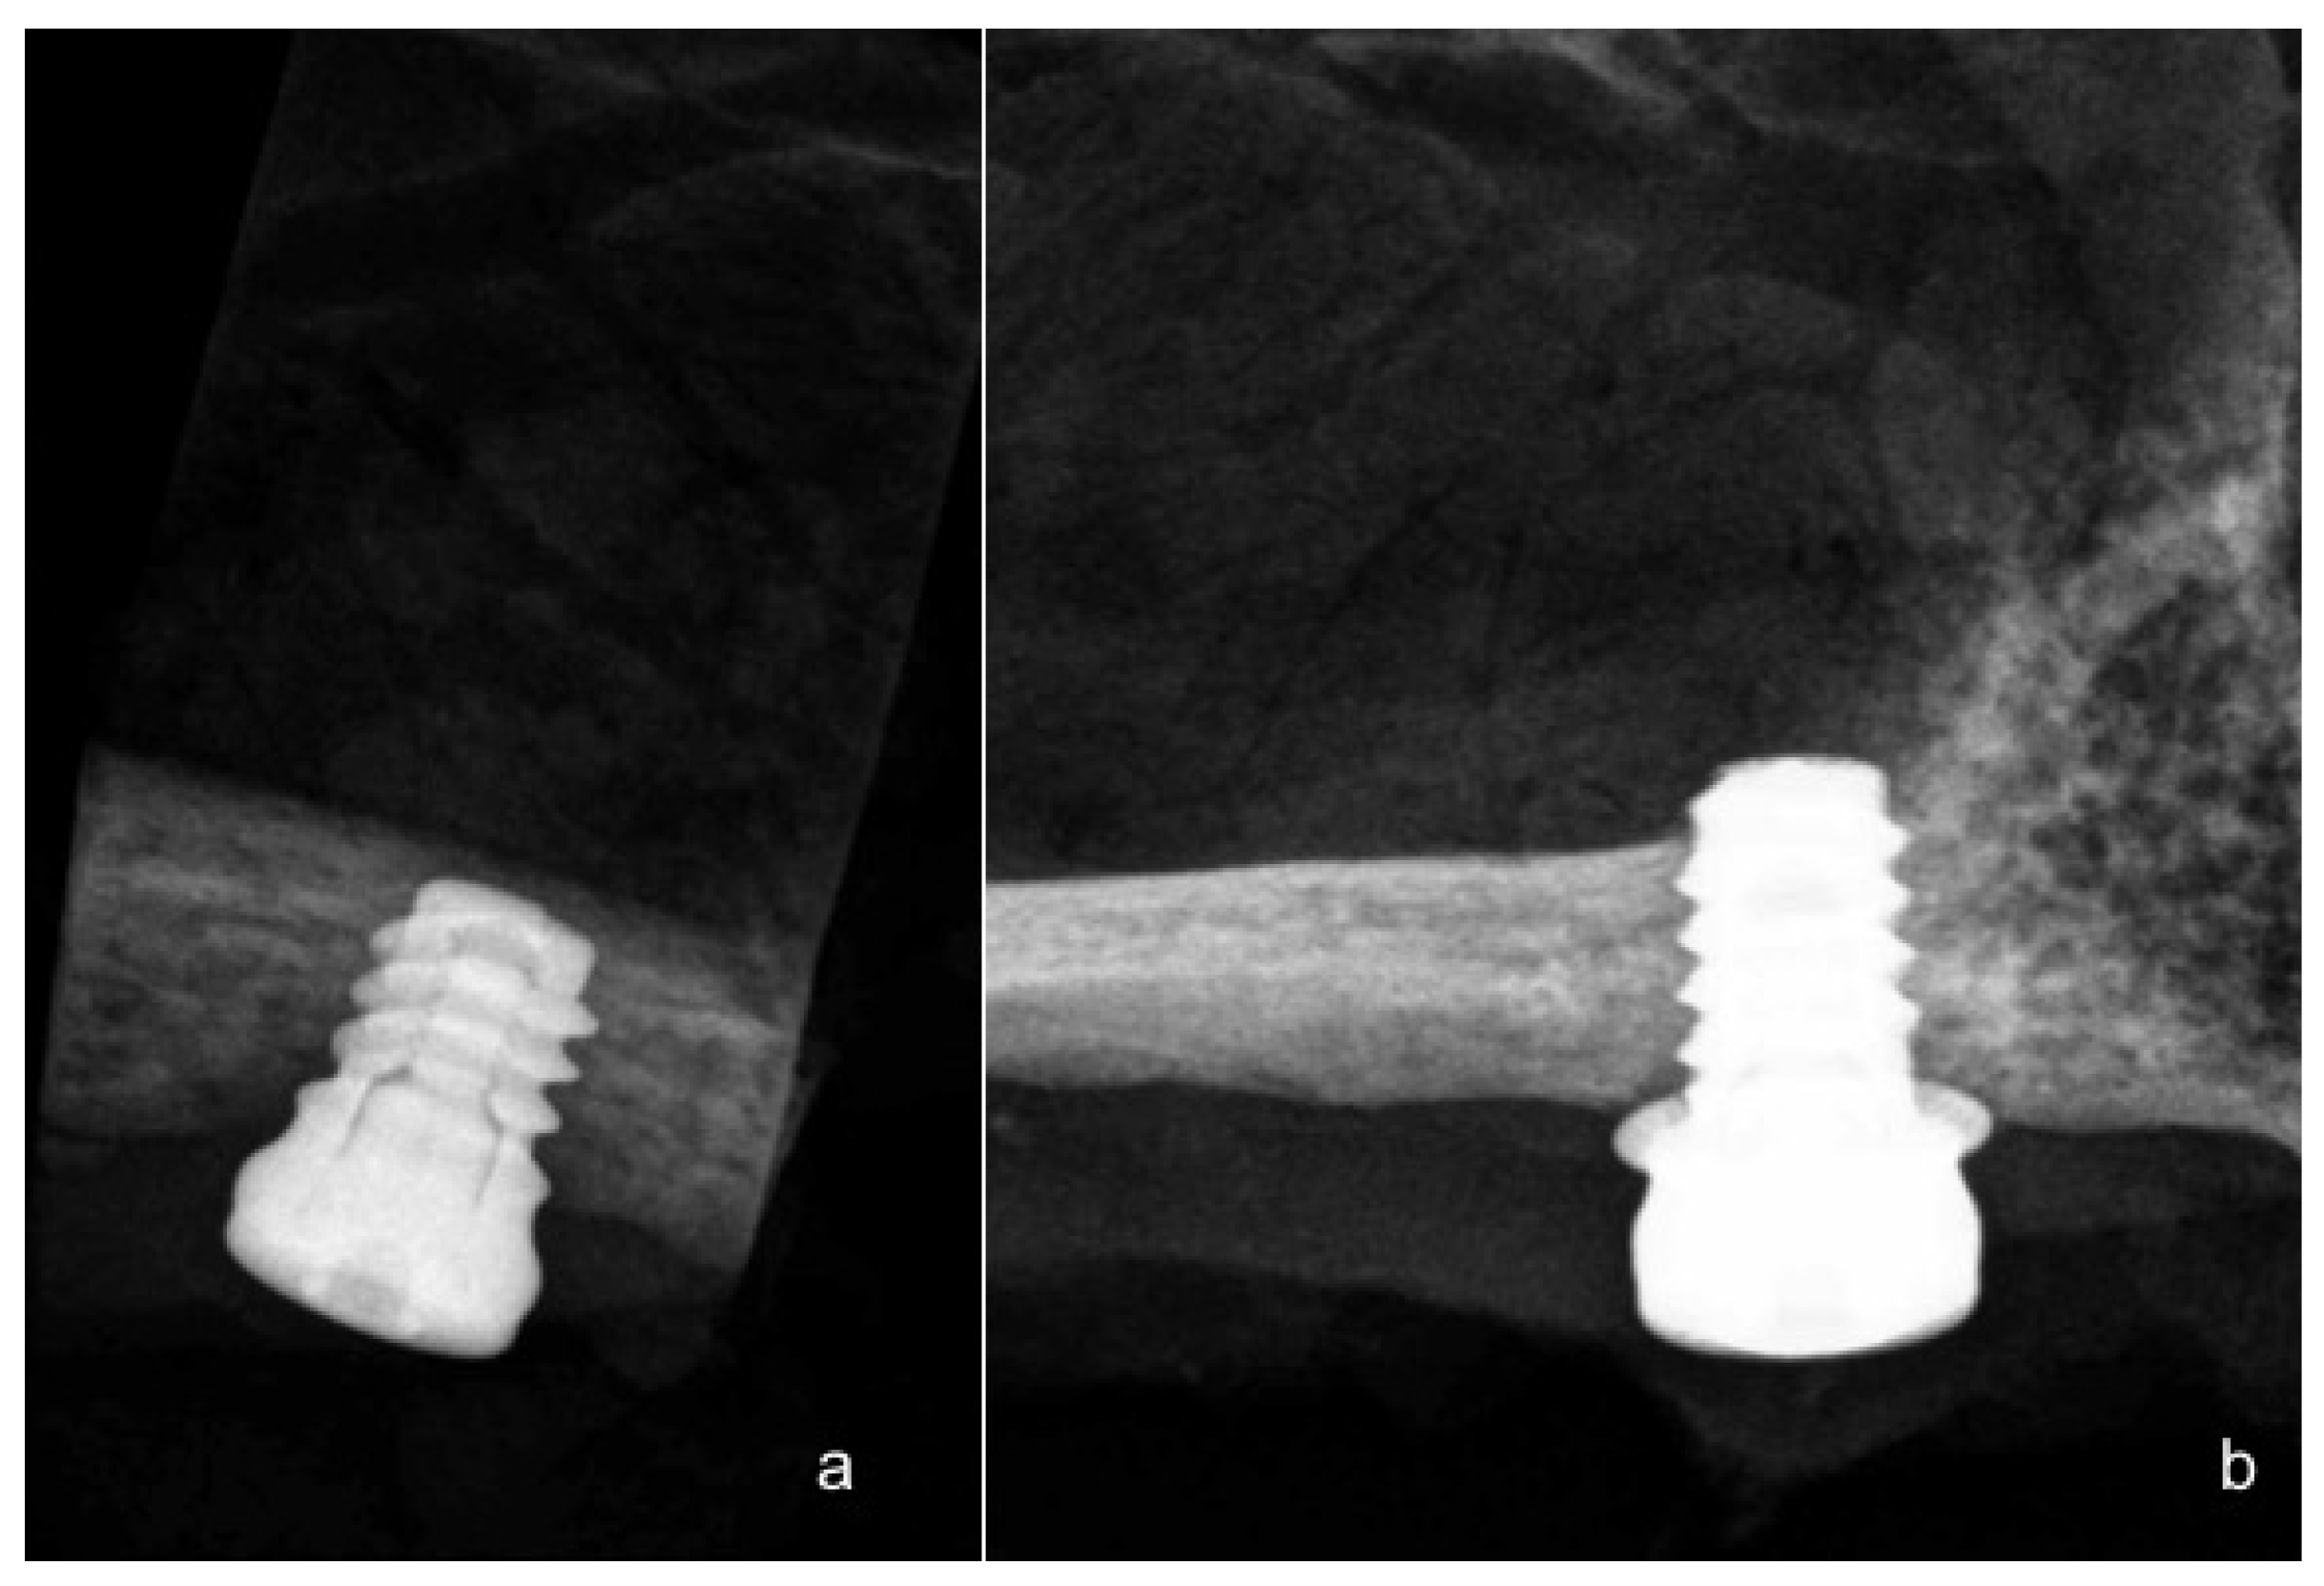

Three of the animals were sacrificed after 8 weeks, and the other three animals were sacrificed after 12 weeks, after the insertion of the implant, through an overdose of Pentothal Natrium® (Laboratorios Abbot, Madrid, Spain), and were perfused through the carotid arteries with a fixative containing 5% glutaraldehyde and 5% formaldehyde. Radiographs were taken after sacrifice at 60 days for the first three dogs, and at 90 days for the remaining three (Figure 4).

Figure 4.

(a) Narrow ring extra-short implant radiograph after 90 days of evaluation; (b) Wide ring extra-short implant radiograph after 90 days follow-up.